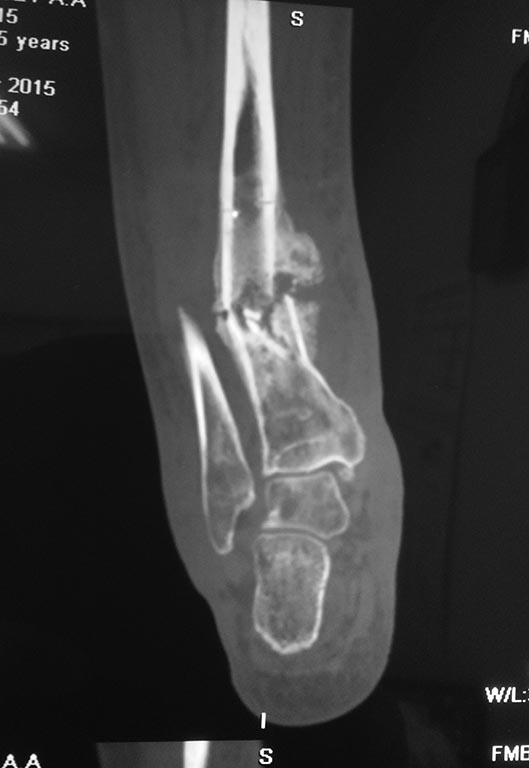

Пациент 45 лет поступил с клиникой открытого перелома левой голени,

обширной рваной раной передней поверхности голени.выполнен остеосинтез

АВФ. Через 3 месяца снятие аппарата. Ношение ортеза с

пневмокоррекцией.После разрешения нагрузки отмечается угловая

деформация голени, формирование псевдоартроза. На данный момент ходит с

тростью, патологической подвижности нет,болевого синдрома в зоне

перелома и области г.стопного сустава нет. рана голени зажила(кожа

истончена, рубцовая ткань в зоне дефекта). Вероятно, необходимо

оперативное лечение, хотелось узнать ваше мнение.